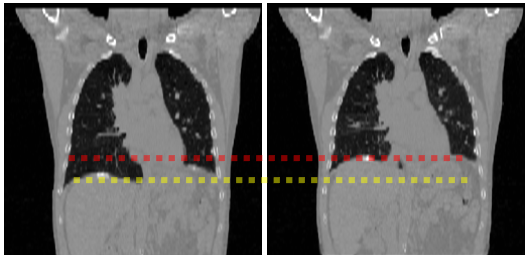

Refer to caption

(a) 4D-C-CT.

(b) 4D-L-CT.

(c) ACDC.

Figure 7: A snapshot of the selected data at two time-points with the largest motion difference: (a) is the 4D-C-CT (axial views) showing the cardiac phases in the end-diastole (ED) and end-systole (ES), respectively of left and right; (b) is the 4D-L-CT (sagittal views) depicting the lungs in the states of maximum breath holding and minimum exhalation. The red line and yellow lines highlight the volume changes of the lung between two phases. (c) is the ACDC depicting the cardiac MR images in the ED and ES, respectively of left and right.

Fig. 7(a) shows a snapshot of randomly sampled cardiac volume slices from a sequence. The 4D-C-CT dataset consists of 18 subjects, each having 5 time-points (image volumes) capturing half cardiac cycle from ED to ES. Since the dataset contains several patients with left ventricular aneurysm resulting in abnormally subtle deformation, we select 12 patient data with large volume changes (volume changing rate from 0.37 to 0.75), and only test on these selected challenging datasets. Each volume is characterized by a high intra-slice (x- and y-) resolution ranging from 0.32 to 0.45mm and inter-slice (z-) resolution from 0.37 to 0.82mm.

IV-A2 4D-L-CT

Fig. 7(b) shows a snapshot of lung volume slices from a sequence. The 4D-L-CT dataset consists of 20 patients, each having 10 time-points representing the whole respiratory cycle. 4D-L-CT images were acquired using a 16-slice, helical CT scanner (Brilliance Big Bore, Philips Medical Systems) with a slice thickness of 3 mm and 512×512512512512\times 512 axial resolution (1similar-toabsent1\sim 1 mm pixel size).

IV-A3 ACDC

Fig. 7(c) shows a snapshot of cardiac MR middle slices from a sequence. The ACDC dataset consists of 100 patients, each having multiple time-points representing the whole cardiac cycle. It has lower imaging resolution - the in-plane voxel spacing ranges from 1.37 to 1.68 mm and the inter-slice spacing ranges from 5 to 10mm. Note that, as inter-slice spacing is large in ACDC, we have to change all the comparisons to 2D, and evaluate on three middle slices in each volume.